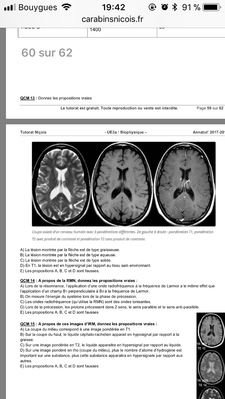

Maintenant pour le qcms 13 le fleche montre une lesion en hypersignal et c’est dit que c’est une image est ponderer en T1 donc la lesion est forcement graisseuse du coup je comprend pas pk A et D sont fause